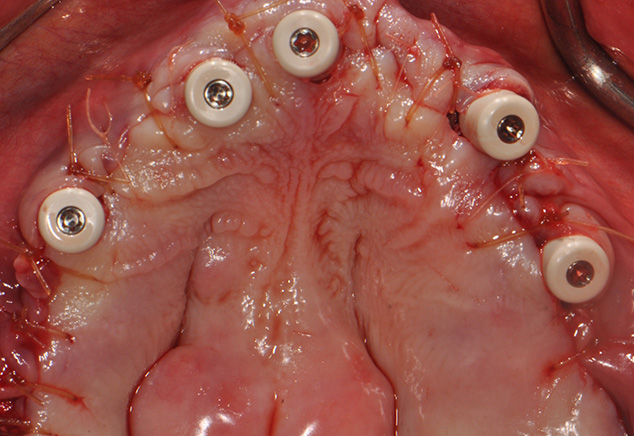

The implant sites were prepared using the manufacturer's protocol (except for bone tapping) for the Straumann BLT implant. The implants were placed using the surgical guide template with the following insertion torques measured: site: #4, #7, #8-9,#11,#13, #21,#23,#26. All torques were >35Ncm with #28 recording 20Ncm insertion torque values. All implants were 4.1mm in diameter and 14mm in length except #7, #8-9, and #11, which were 12mm in length (Fig 7). All 17 and 30 degree-angled implants were bone profiled prior to SRA abutment placement. This allowed the complete seating of the SRA abutment at the recommended 35Ncm torque. Using the available Straumann bone profilers with the appropriate Narrow Connection (NC) or Regular Connection (RC) inserts was a critical step for an abutment to fit correctly. The following SRA abutments (all were 2.5mm gingival heights) were then chosen: straight: #23, #26; 17 degrees: #4, #7, #8-9; and 30 degrees: #11, #13, #21, and #28. Tall protective healing caps were then placed (Fig 8), and the dentures were checked to evaluate that there was adequate space for the pink acrylic to allow for bite registration material thickness. All sockets and buccal gaps to the immediately placed implants were bone grafted. Prior to suturing, the tissue flaps were scalloped with 15c blades to reduce overlap of the flaps over the protective caps. This not only aided in post-operative healing, but also aided in the visualization of the abutments by the restorative dentist for the provisional insertion. The patient was sutured with resorbable 4-0 chromic gut and 5-0 Vicryl™ sutures (Ethicon: Johnson & Johnson) and was released to be seen immediately by Dr. Randel for the coordinated restorative visit. As discussed below, his responsibilities included: bite registration, impressions, and the dental lab conversion of the complete denture to a metal reinforced fixed transitional prosthesis (indirect provisionalization technique). Our team of restorative dentists have been treating full-arch immediately loaded cases on 5-8 implants (depending if restoration is a hybrid or C&B) since 1994. Our earlier experiences, for approximately the first two years (1994-1996), have us all presently using the indirect technique, which in our hands is easier for everyone involved (especially the patient). We handle these coordinated visits between offices, the dental lab, and our Straumann representative weeks prior so we are all on the same page with timing. These coordinated efforts could be compared to a symphony orchestra, where each musician knows their specific part and when and where they are expected to be. Many of our patients have described this fluidity as a seamless experience that they witness first hand and greatly appreciate.

The next afternoon, the prostheses were inserted (Fig 10) and panoramic radiographic confirmation of proper seating was obtained (Fig 11). Any necessary occlusal adjustments were then completed. The patient was then seen every 2-3 weeks for deplaquing and plaque control review per our earlier discussed protocol. The occlusion was also refined as needed. A water irrigation device was given and reviewed at 6 weeks post-surgery.